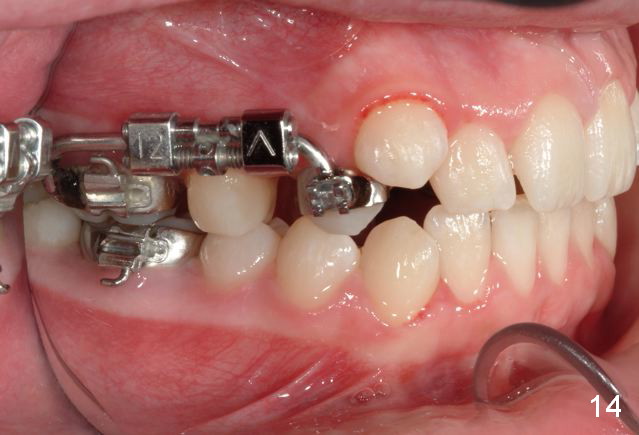

Rapid Molar Distalizer is placed (Fig.11). It is turned twice a week. UR6,7 are bodily distalized to Class I with gaining of the arch length 4 months 11 days later (Fig.12,14) without adverse effect on U midline (Fig.13). Final result?